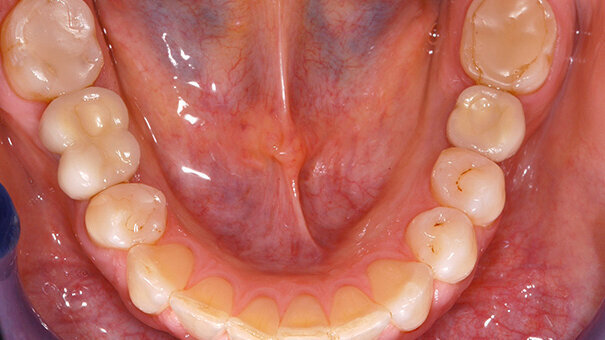

A 41 year old woman came to our clinic with missing first molars on both sides of the mandible (Figure 1). The patient was healthy, with a good oral hygiene, she was a non-smoker and with good compliance. This made her a good candidate for implant treatment.

After soft tissue healing, impression copings were connected to the implants (Figure 6 and 7), note the good position and direction of the implants.

The definitive prostheses were tried in (Figure 13 and 14). Articulating foil was used to avoid direct occlusal contacts. The screw access holes were closed after try in and delivery (Figure 15). Good contact of the screw retained implant reconstruction to the adjacent teeth is important to avoid food impaction. The cantilever must be able to clean with super floss or at least with inter dental brushes.

Figure 16 and 17 show the clinical situation after 11 years. Note how stable the soft tissues have remained over time. The bone levels also remained stable over the entire 11 years. Figure 18-21 show baseline and 11 year radiographs of both reconstructions. Note how the bone levels are slightly higher after 11 years than at time of impression.